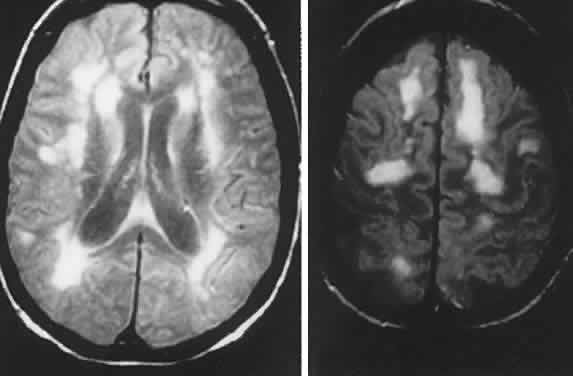

The late infantile type (Bielschowsky-Jansky) is a fatal recessively inherited disorder with genomic defect localized to chromosome 13q22, thus delineating this disease as a separate entity.32 Presentation is with developmental arrest and seizures at 2 to 5 years of age, with motor and visual symptoms thereafter. There is massive tissue accumulation of lysosomal hydrophobic subunit-c protein of the mitochondrial adenosine triphosphate synthase. Ganglion cells are decreased in number, with thinning of the nerve fiber layer and optic atrophy. In addition, there is involvement of the outer segments with degeneration of the rods and cones and pigmentary clumping in the outer retinal layers. On MRI, hyperintense periventricular signals correlate with severe loss of myelin.33

Optic nerve involvement may occur in the mucopolysaccharidoses (MPS), taking the form of optic atrophy or papilledema. Although true papilledema doubtlessly occurs in association with hydrocephalus seen in these disorders, there are other instances of “papilledema” in which fundus descriptions or photographs are not convincing. Goldberg and Duke35 reported the ocular histopathologic findings in a patient with Hunter's syndrome (MPS II), in which premortem examination included the observation of “bilateral chronic papilledema.” On microscopic examination, the optic nerve was normal, despite marked retinal pigmentary degeneration, showing neither consecutive atrophy nor changes compatible with chronic papilledema. Similarly, Kenyon and colleagues36 reviewed the systemic mucopolysaccharidoses and included an instance of a 26-year-old man with Hunter's syndrome (MPS II), whose ophthalmoscopic examination revealed “blurred disc margins in both fundi (without venous congestion, hemorrhages or exudates) compatible with mild chronic papilledema,” but no further comment was made in elucidation of this finding. Hunter's syndrome is an X-linked recessive disorder characterized by facial and skeletal dysmorphism, stiff joints, and mental slowing. Deafness and chronic disc edema occur, without raised intracranial pressure, and mucopolysaccharide deposition in the sclera and optic nerve septa, especially at the lamina cribrosa, is described.37 MRI may disclose large multifocal cystic areas of hypointense or hyperintense signals in white matter, including the corpus callosum, likely reflecting deposition of mucopolysaccharide and increased fluid content.38